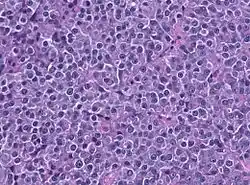

Das Prolaktinom ist ein gutartiger Tumor (Adenom) des Hypophysenvorderlappens (Adenohypophyse), der Prolaktin produziert. Dies führt zu einem Überschuss von Prolaktin im Blut, einer sogenannten Hyperprolaktinämie. Es ist bisher nicht sicher bekannt, wodurch ein Prolaktinom entsteht.